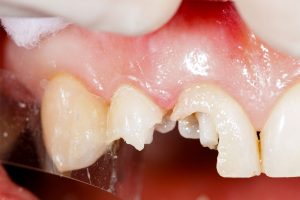

Affordable Wisdom Tooth Extractions in Brampton – Pricing & Options Explained Worried about the cost of removing a wisdom tooth? You’re not alone. Many patients delay wisdom tooth extraction due to uncertainty about pricing — but doing so can lead to worse problems down the road. At Polaris Dental in